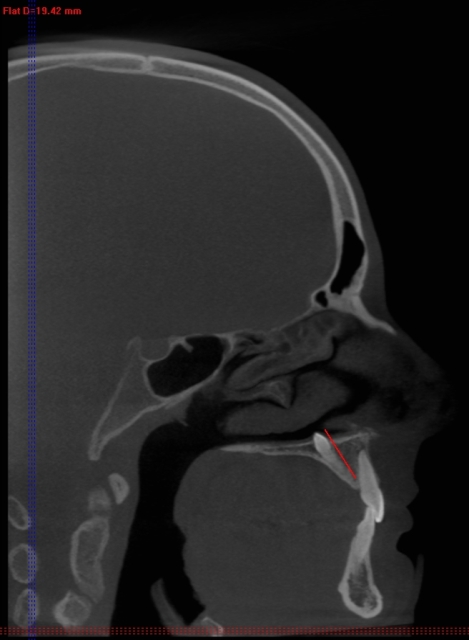

Za razliko od običajnih CT-naprav, kjer rentgenski snop prodira skozi tkivo v ravninah in slika nastane z obdelavo vseh »rezin«, ki so različno narazen (običajno 1 do 3 mm), pri CT-napravah s stožčastim snopom detektorji sprejemajo stožčast snop – podatki dajo sliko prostornine in ne samo ravnine. Naprave so precej manjše, pacientu ni treba ležati, odmerek sevanja, ki ga prejme pacient, je okrog 50-krat manjši, kot pri običajnih CT preiskavah, slika trdih tkiv (torej kosti in zob) pa je neprimerno ostrejša (slike 2, 3, 4).

Slike 2, 3, 4: Posnetki CT-ja s stožčastim snopom. Položaj nadštevilčnega zoba je jasno prikazan v vseh treh ravninah, lepo se vidi, da zob s krono sega v nosno votlino. Zob je mogoče natančno izmeriti.